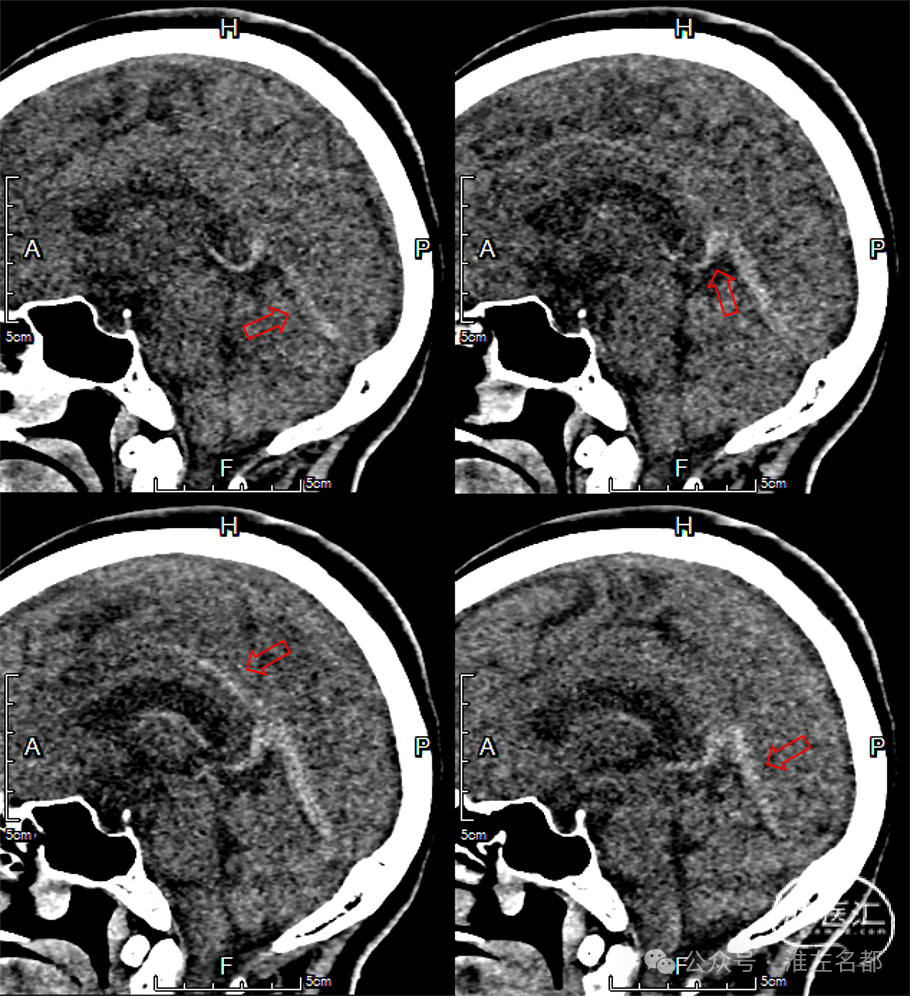

颅脑MRI

2024-9-25

T2

双侧丘脑和右侧内囊-间脑淤血性梗死、水肿和伴渗血。

增强MRV:左侧横窦-乙状窦显影纤细;上矢状窦和右侧横窦-乙状窦充盈缺损;脑深部静脉和直窦未见显影。

SWI:双侧丘脑渗血改变,右侧基底静脉和大脑中静脉血栓。

三维黑血高分辨T1

三维黑血高分辨T1平扫(上图)和增强(下图):右侧乙状窦慢性血栓,平扫呈等低信号,并显著强化。

三维黑血高分辨T1平扫(上图)和增强(下图):右侧横窦慢性血栓。

三维黑血高分辨T1平扫(上图)和增强(下图):上矢状窦慢性血栓;直窦内新进血栓(急性血栓等低信号,或亚急性血栓高信号,无强化)。

三维黑血高分辨T1平扫(上图)和增强(下图):左侧横窦发育细小。

三维黑血高分辨T1平扫(上图)和增强(下图):左侧乙状窦局部未发育。